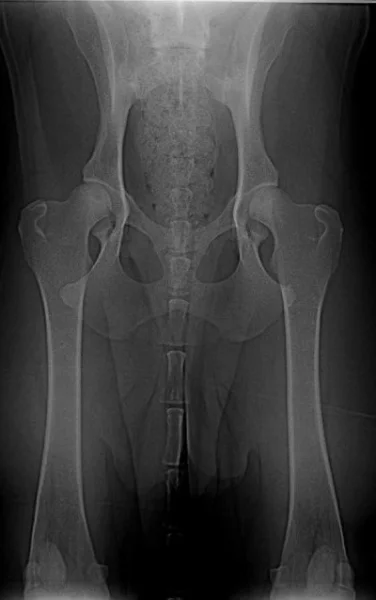

Grifovi je dnes skoro sedm let, a navzdory předpovědím chodí. A velkou zásluhu na tom má plavání. Podívejte se na rentgeny a přečtěte si jak se nám to podařilo. Tímto článkem bych také chtěl dát trochu naděje těm, kteří mají štěně či psa, který přestal chodit a má dysplazii kyčlí.

Znovu na rentgenu jsme byli ve zhruba čtyřech letech, kdy Grif prodělal amputaci plovací blány, protože se mu po zánětu udělala boule velikosti velkého vlašského ořechu. Rentgen, který zde vidíte je poslední, ze skoro sedmi let, kdy jsme byli na operaci s předním loktem, artrózu bylo nutné odfrézovat. Ano, to byla poslední zatím neoperovaná noha. Pro přehled je vedle další rentgen zdravého psa (mladého leonbergera). Prohlédněte si oba klouby.